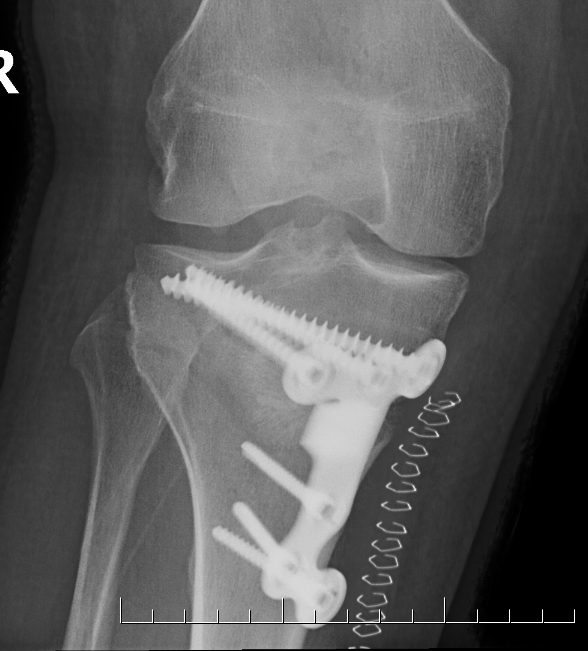

Classification lateral hinge fracture after OW HTO

Takeuchi classfication

- type I: extend into lateral cortex above proximal tibio-fibular joint

- type II: extend into lateral cortex below proximal tibio-fibular joint

- type III: extend into lateral tibial plateau

Type II hinge fracture

Management

Type I: limit weight bearing 6 weeks

Type II / displacement: lateral plate

Instability

- place a Richards staple / plate over lateral fracture site